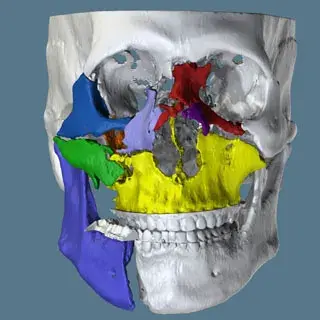

3D Systems' VSP® surgical planning solutions for craniomaxillofacial (CMF) applications received FDA clearance as a service-based approach to personalized surgery over 10 years ago.

3D Systems and Stryker Corporation have partnered to provide surgeons with best-in-class products and services for craniomaxillofacial surgeries. As a leader in personalized healthcare solutions, 3D Systems has planned and delivered devices for more than 140,000 patient-specific cases. The Stryker Craniomaxillofacial business specializes in providing patient-specific options and innovative solutions that help drive efficiencies in surgical suites. The combination of Stryker’s specialized team and advanced implants with 3D Systems' cutting-edge 3D printing technologies and expert consulting services positions both companies to provide a superior level of service to healthcare professionals who use these revolutionary solutions.